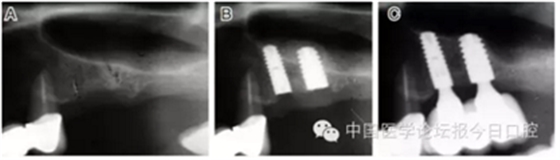

病例2 骨質(zhì)較少(圖4)

圖4